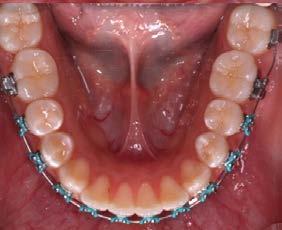

Caso clínico: paciente femenino de 19 años, patrón dolicofacial, perfil convexo, clase II esqueletal debido a una retrusión mandibular, mordida abierta anterior esqueletal, clase II molar, clase canina no establecida por mordida abierta, apiñamiento severo superior e inferior y deglución atípica.

Resultados: obtención de una clase canina I y clase molar II funcional, se corrigieron las sobremordidas horizontal y vertical, y se logró la coincidencia de líneas medias facial y dental. El manejo de la mordida abierta anterior se llevó a cabo por medio de la corrección del hábito de deglución atípica con la ayuda de spikes de resina, elásticos intermaxilares y arcos utility, y se obtuvieron buenos resultados estéticos, dentales y funcionales.